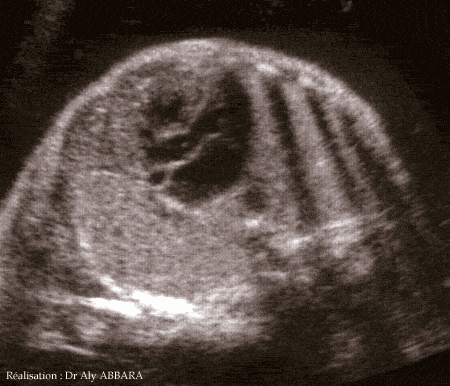

Cœur fœtal à 30 semaines d'aménorrhée

Mise en évidence de la continuité aorto-septique et aorto-mitrale